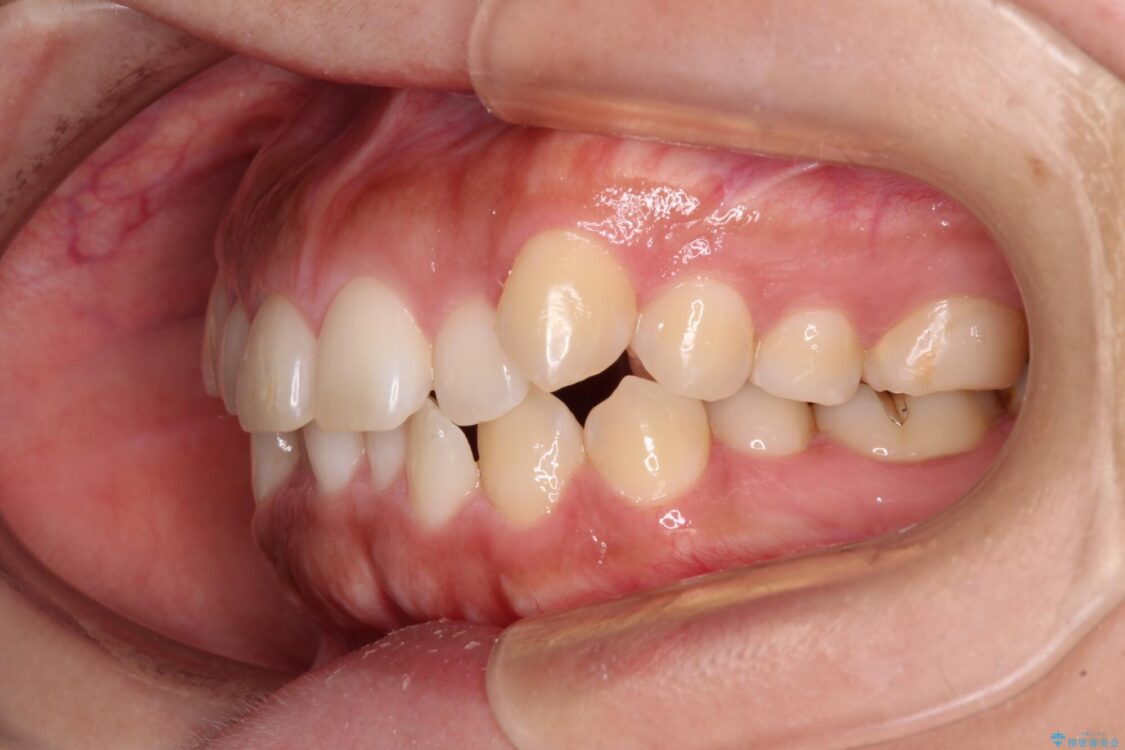

治療後

• 【モニター】カリエール・ディスタライザーを併用した八重歯のインビザライン矯正 治療後画像

カリエールディスタライザーを併用したことで、すっきりとした口元になり、上下の正中を合わせることができました。